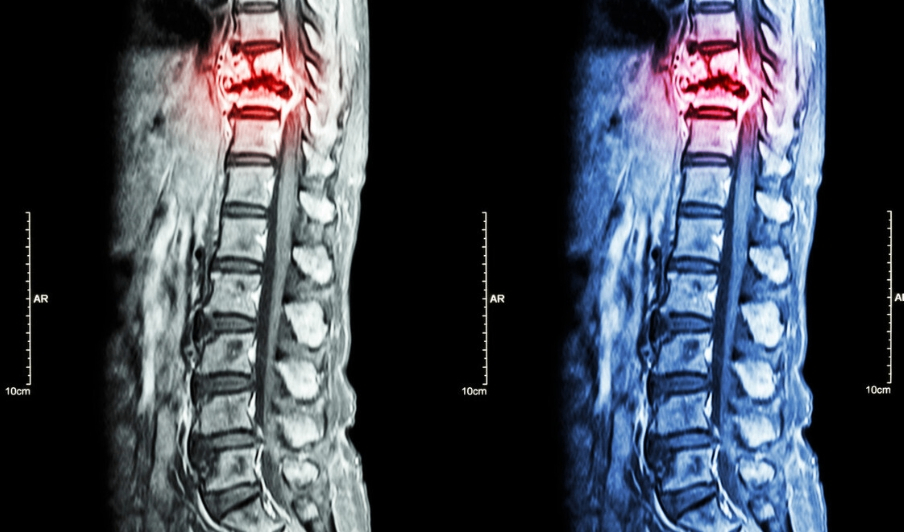

放射性核素全身骨扫描是诊断骨转移的主要手段,包括X线、CT、MRI(磁共振)、ECT(放射性核素骨扫描)、PET-CT(正电子发 射型计算机断层显像)等。

CT和MRI能够发现更早期的转移病灶,MRI尤其在判断脊柱转移癌是否压迫神经上更具优势。

2. 骨病灶经 X 线平片,或 MR 扫描,或 CT,或 PET-CT 检查证实骨破坏,并诊断为恶性肿瘤骨转移。

经过核磁检查示:L1椎体及左侧附件异常信号。后又在北京大学人民医院查肿瘤标志物后,显示多项指标异常。